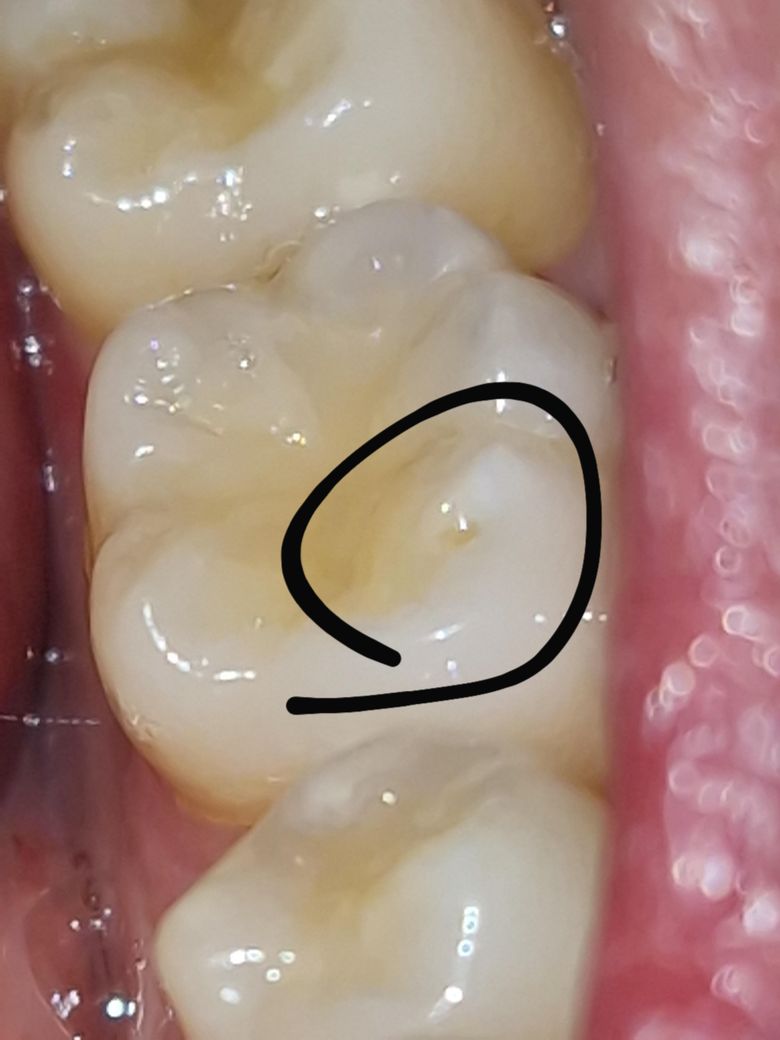

이빨에 홈같은게 있어요. 충치인가요?

어금니 쪽에 홈같은게 있어요 시리거나 아프거나 하지는 않았는데 이빨에 홈인지 얼룩인지 모를게 보여요. 예전에 레진으로 떼우는 치료를 했는데 그때 난건지, 충치인지 궁금합니다

사진으로 봤을 경우에는 충치로 보이진 않습니다 대신에 레진으로 한 부위의 치아색이 변해질 가능성이 있습니다. 크게 문젠 되지 않지만 신경에 쓰인다면 레진을 교체할 수 있습니다. 자세한 확인을 위해서 치과에서 진료를 받아보는 것을 권유드립니다.

충치로 보이지는 않으며 원래 조직 모양이 그럴 수도 있고 외상에 의해 치아가 깨졌을 수도 있습니다.

사진이 흐려 마모 때문인지 아니면 이전에 레진 한 것이 빠진 것인지 확실하지 않지만 치과에 가서 치료 받아야 합니다.

충치는 아니고 치아를 사용하면서 교모가 되면서 생긴 홈입니다 크게 걱정은 안하셔도 될것같습니다.

충치는 아니고 단순 치아 파절, 마모같습니다 떼워주면 좋은데 꼭 떼워야 할 정도로 큰 파절은 아닙니다